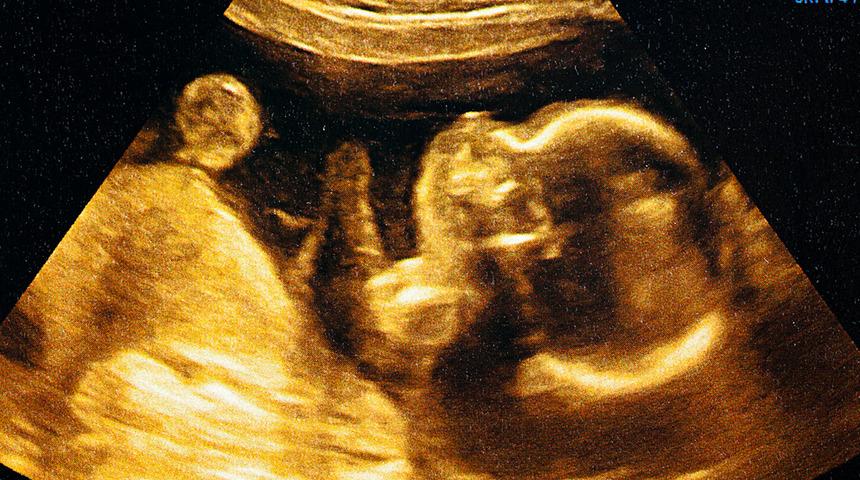

Anne karnında regresyon ile ceninken yaşadığınız travmalar gün yüzüne çıkıyor!

Kişinin zihinsel ve duygusal sağlığını etkileyen olaylara müdahale etmeye olanak tanıyan regresyon, gerileme - geriye gitme anlamıyla öne çıkar. Regresyon terapisi de kişinin geçmiş yaşamının terapi altına alınmasıdır. Kişinin hayatındaki çatışma alanlarına ve olumsuzluklara odaklanılan anne karnında regresyonda henüz ceninken açık olan algılar nedeniyle geçirilen travmalar hedef alınır. Peki anne karnında regresyon terapisi yaptıranlar neler yaşar? Regresyon Terapisti Gülbahar Yeni anlattı.

Anne karnında regresyon, bizler anne karnında henüz bir ceninken açık olan algılarımızı hedef alır. Bu süreçte annemizin iç dünyasını ve çevremizde olup bitenleri algılayabiliriz. Ayrıca anne karnında olduğumuz dönemde atalarımızdan bize enerji aktarımıyla, olumlu ya da olumsuz enerjiler, bilinçaltından ve enerji alanından bize aktarılır.

Anne karnında regresyonda incelenen travmalar anne karnında yaşananları ele almaktadır. Birçok kişi için anne karnında başlayan travmalara neden olabilecek konulara örnek vermek gerekirse; hamilelikte istenmemiş veya düşürülmeye çalışılmış bir bebek, ölü doğumlar, anne karnında bir yakının kaybı, ailede yaşanan erken ölümlere yönelik olarak tamamlanmamışlık hissi, erken veya sezaryenle doğum sonrasında küvözde kalma durumu, ebeveynlerin çocuk olmadan önce veya sonra boşanması, çocukluk yaşlarda taciz olayı yaşanması ve ikili ilişkilerde bu blokajın hala hissediliyor olması, kişinin dayak yemesi ve bu dayağın fiziksel, duygusal, zihinsel bedeninde yaralar açmış olması gibi konulardır.

Dünyanın nasıl bir yer olduğuna ilişkin ilk ve en güçlü algımız, anne karnında geçirdiğimiz 9 aylık dönemde oluşmaktadır. Annenin yaşadığı korku, endişe, umutsuzluk gibi olumsuz duygular olduğu gibi bebeğe geçer. Daha da önemlisi, bebeğin bu duyguları kendisine aitmiş gibi algılamasıdır.